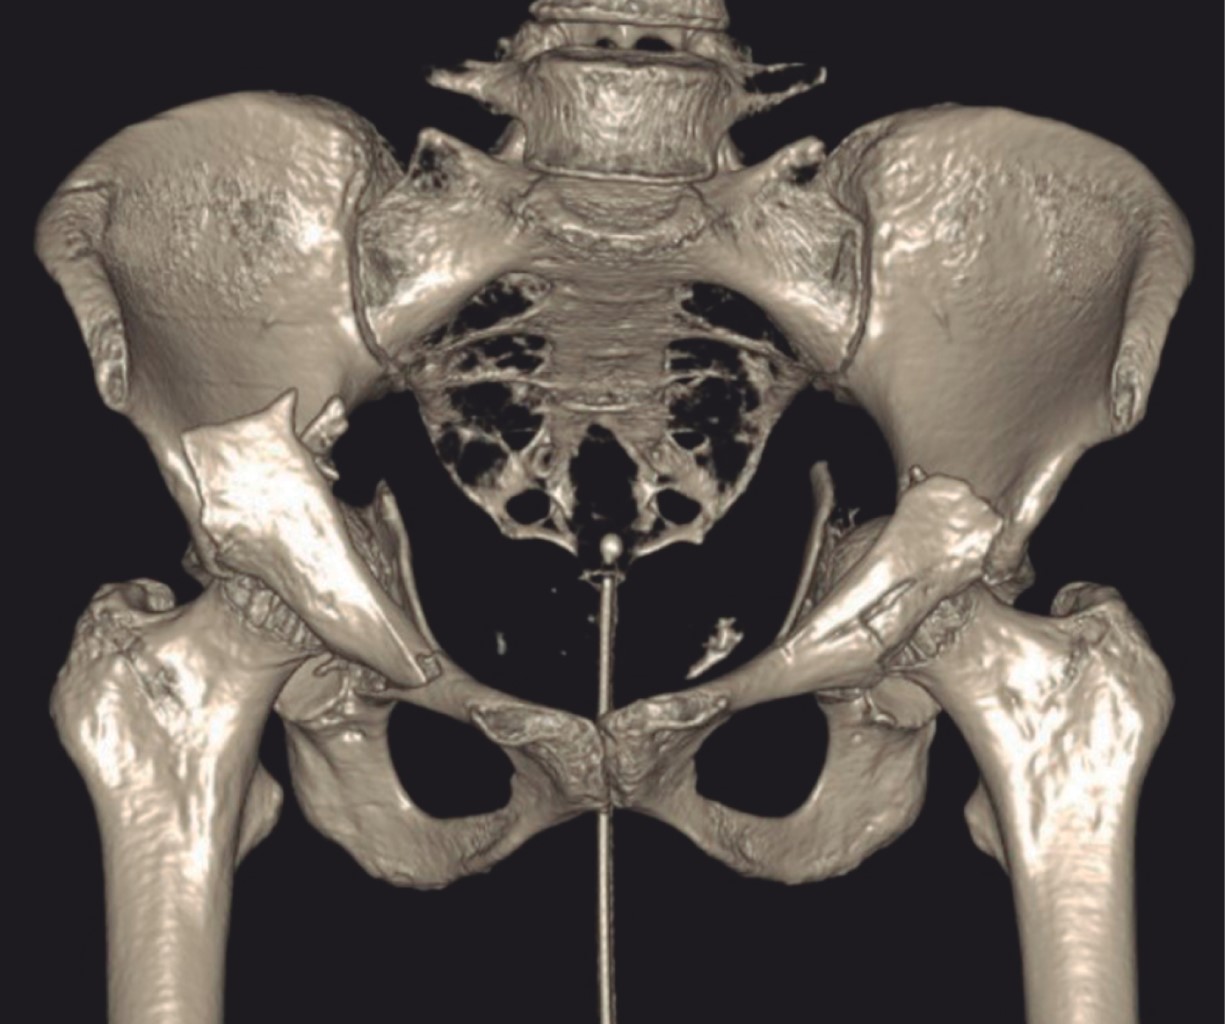

Bilateral acetabular fracture secondary to seizure. Case report and literature review

Introduction: acetabular fractures are generally related to high energy mechanisms. A case report and literature review are exposed. There are few publications with reports of bilateral acetabular fractures secondary to seizures, a total of 26 case reports, no citations in the Mexican population. Objective: to present a case of bilateral fracture of the acetabulum associated with convulsive crises, its management and clinical evolution. As well as a review of the literature and injury mechanims. Clinical case: a 68-year-old female patient who debuted with an episode of seizures, presenting with a bilateral fracture of the AO acetabulum type 62B3.3/Judet, I. Performing surgical management, through open reduction and internal fixation using a modified Stoppa approach with two plates. 9-hole curved reconstruction plates for the left acetabulum and one open reduction and internal fixation with two 10-hole reconstruction plates and one 6-hole spring plate for the right acetabulum, presenting excellent functional results. Conclusion: the injury mechanims of acetabular fractures continues to be of high energy, with few cases associated with seizures reported in the literature. Inevitably the patient will evolve to a post-traumatic coxarthrosis; the initial management with osteosynthesis and acetabular reconstruction is focused on the future definitive treatment with bilateral total hip arthroplasty with primary components, so far the result is encouraging.

Figure 2